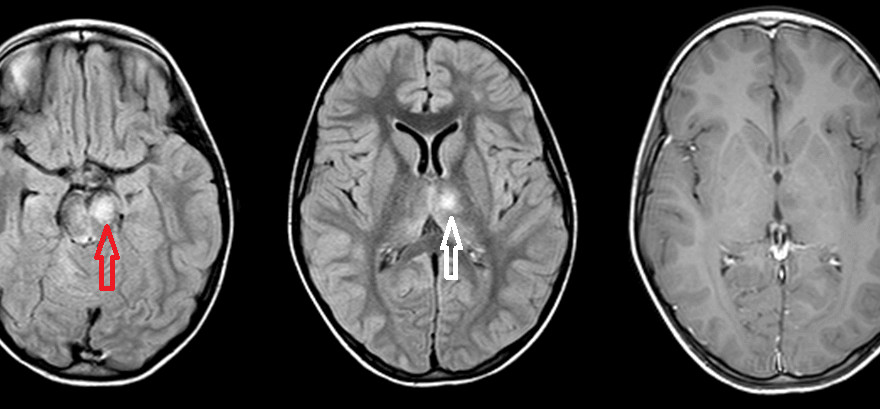

Figure: Axial FLAIR at the level of the midbrain (A) and the thalamus (B) demonstrate increased signal in the left anteromedial thalamus (red arrow) and ventral midbrain (white arrow). Axial postcontrast T1 demonstrates no enhancement of the thalamic signal abnormality (the midbrain abnormality also did not enhance but is not shown).

Unlike MS, ADEM does not typically involve the calloseptal interface (the inferior surface of the corpus callosum immediately adjacent to the septum) and it often involves the deep grey matter (thalamus, basal ganglia, dentate etc).